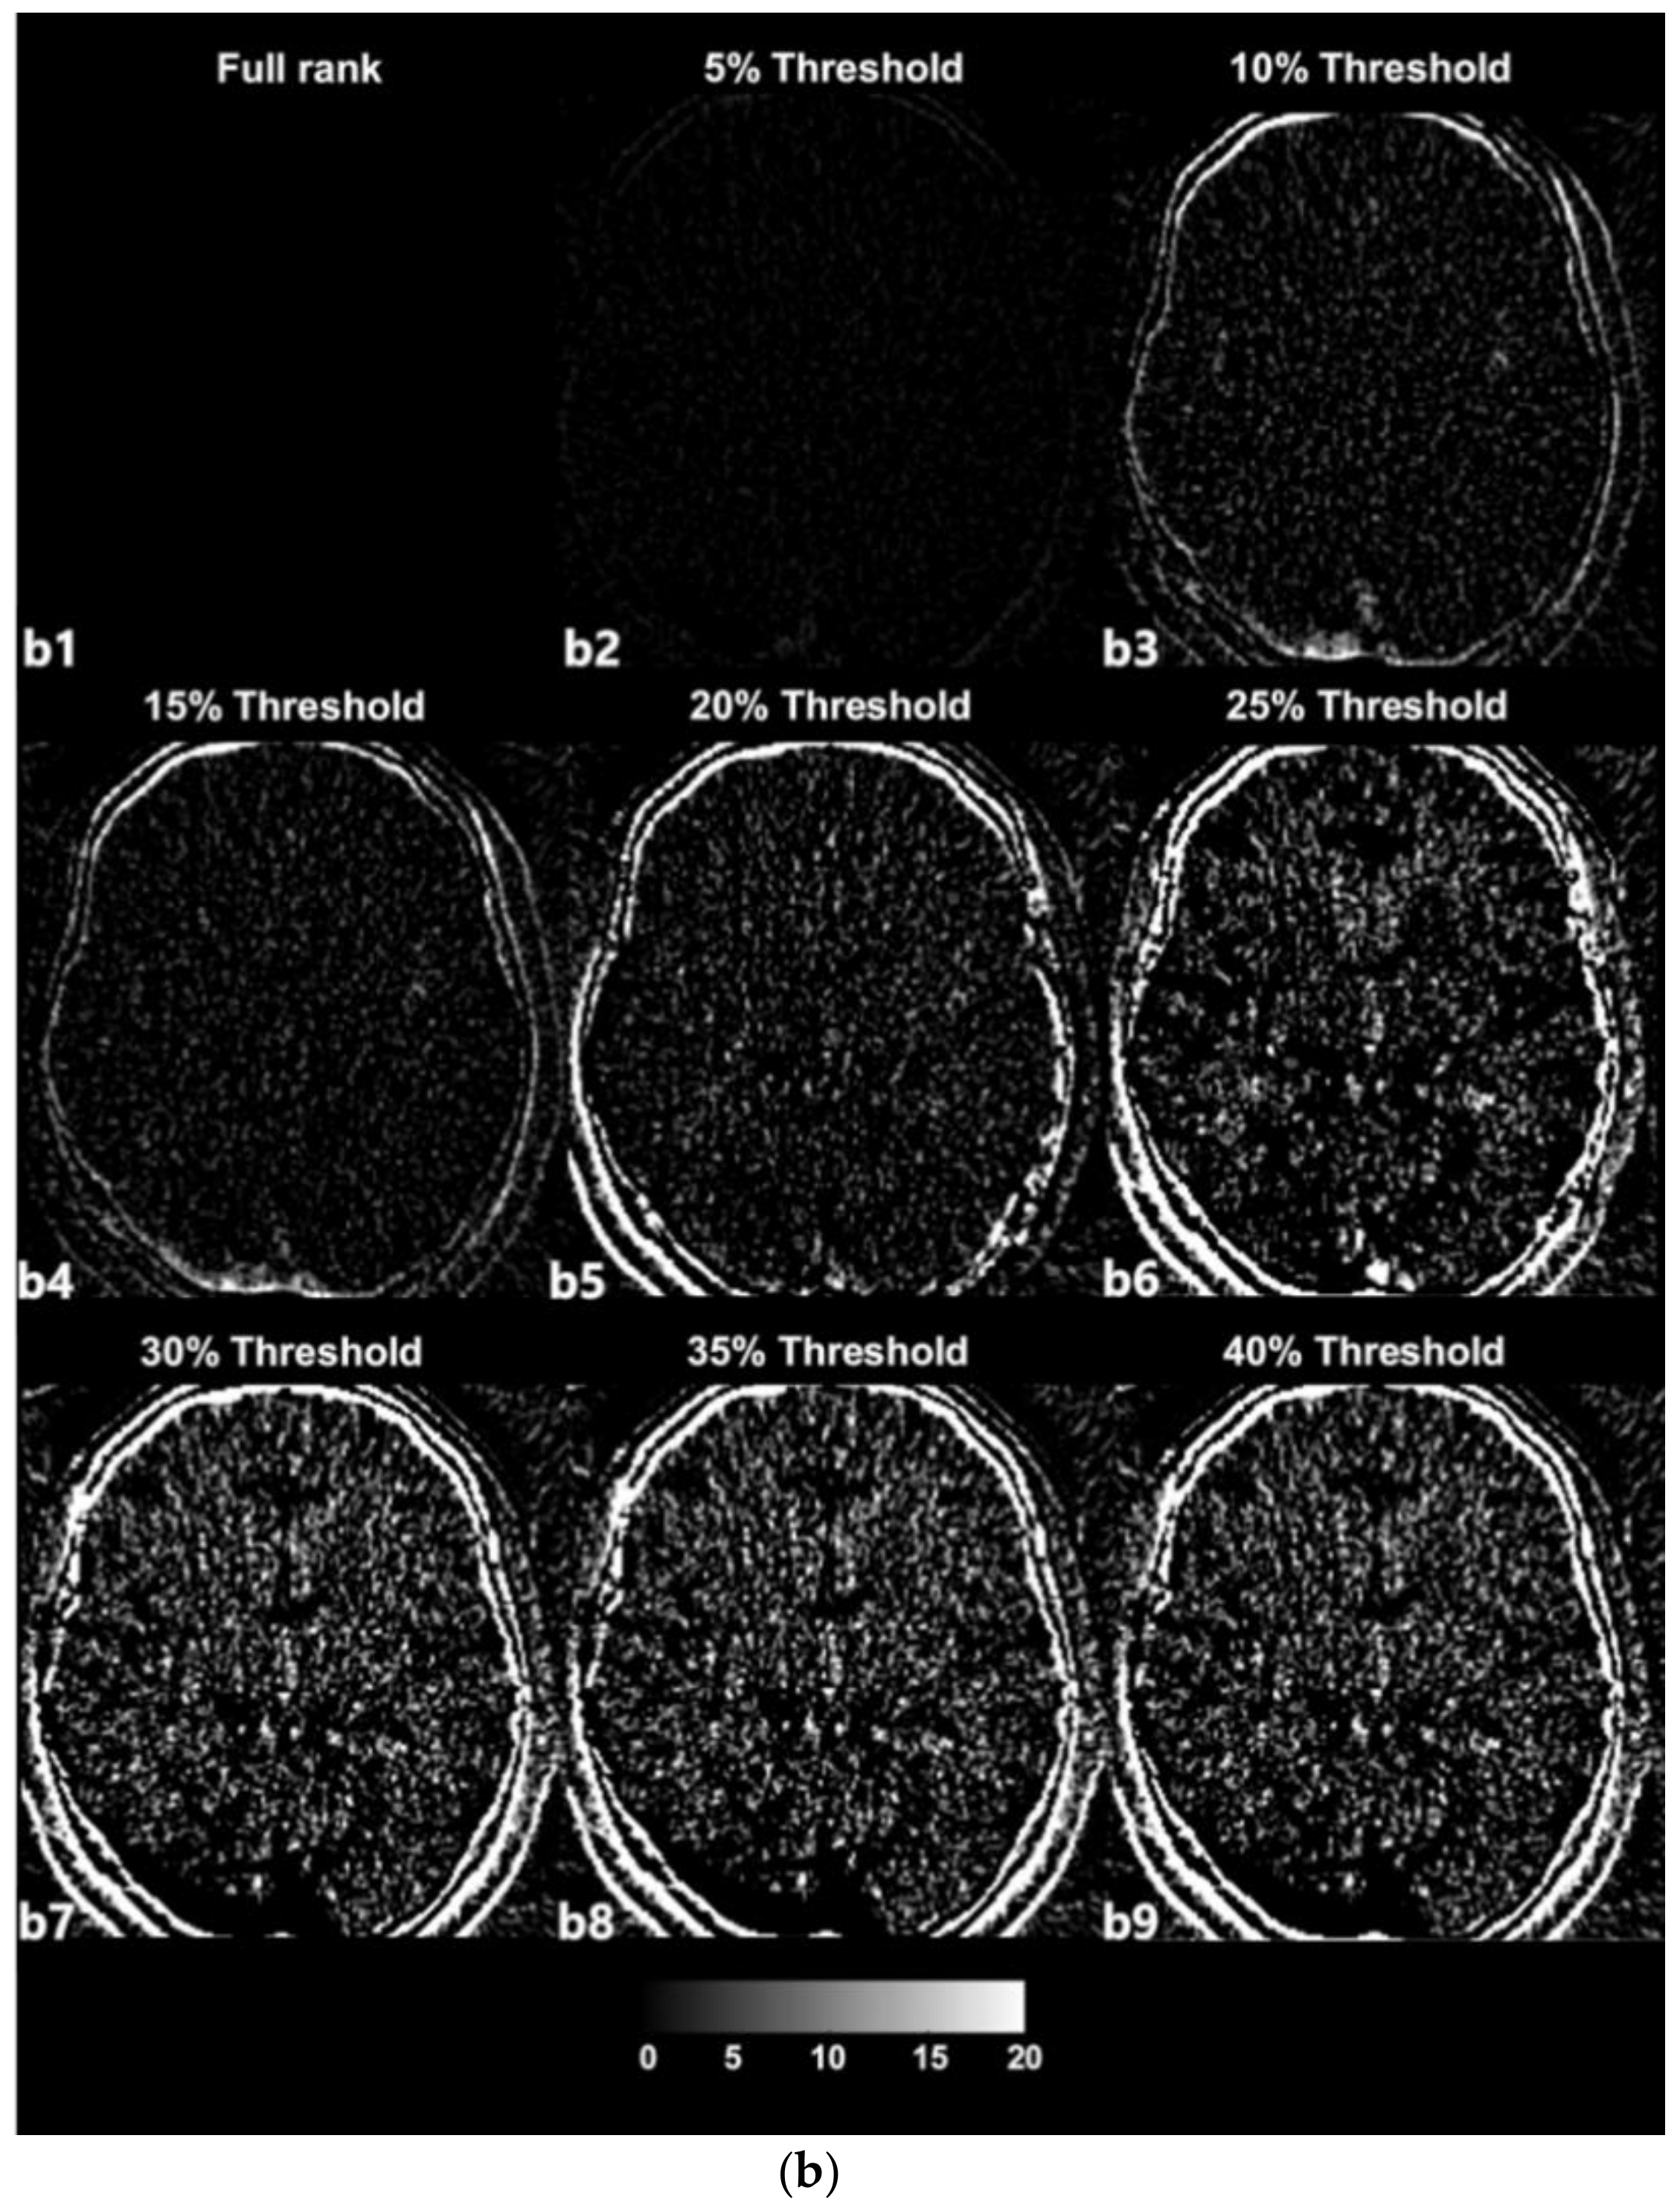

3.1. SVD-Based Noise Removal